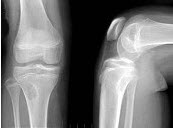

85、单项选择题

男,72岁,手足小关节红肿热痛,白细胞升高,血沉快,血尿酸升高,结合图像,最可能诊断是()

A.类风湿关节炎

B.退行性骨关节病

C.痛风性关节炎

D.假痛风

E.滑膜炎